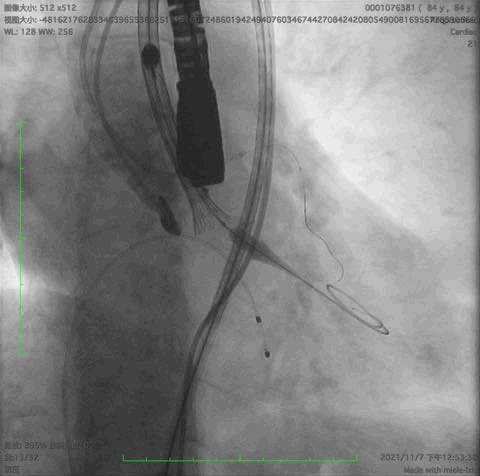

主动脉根部造影,冠脉开口保护

释放到1/3处造影

释放到回收极限造影

瓣膜完全释放后造影,形态良好,无瓣周漏